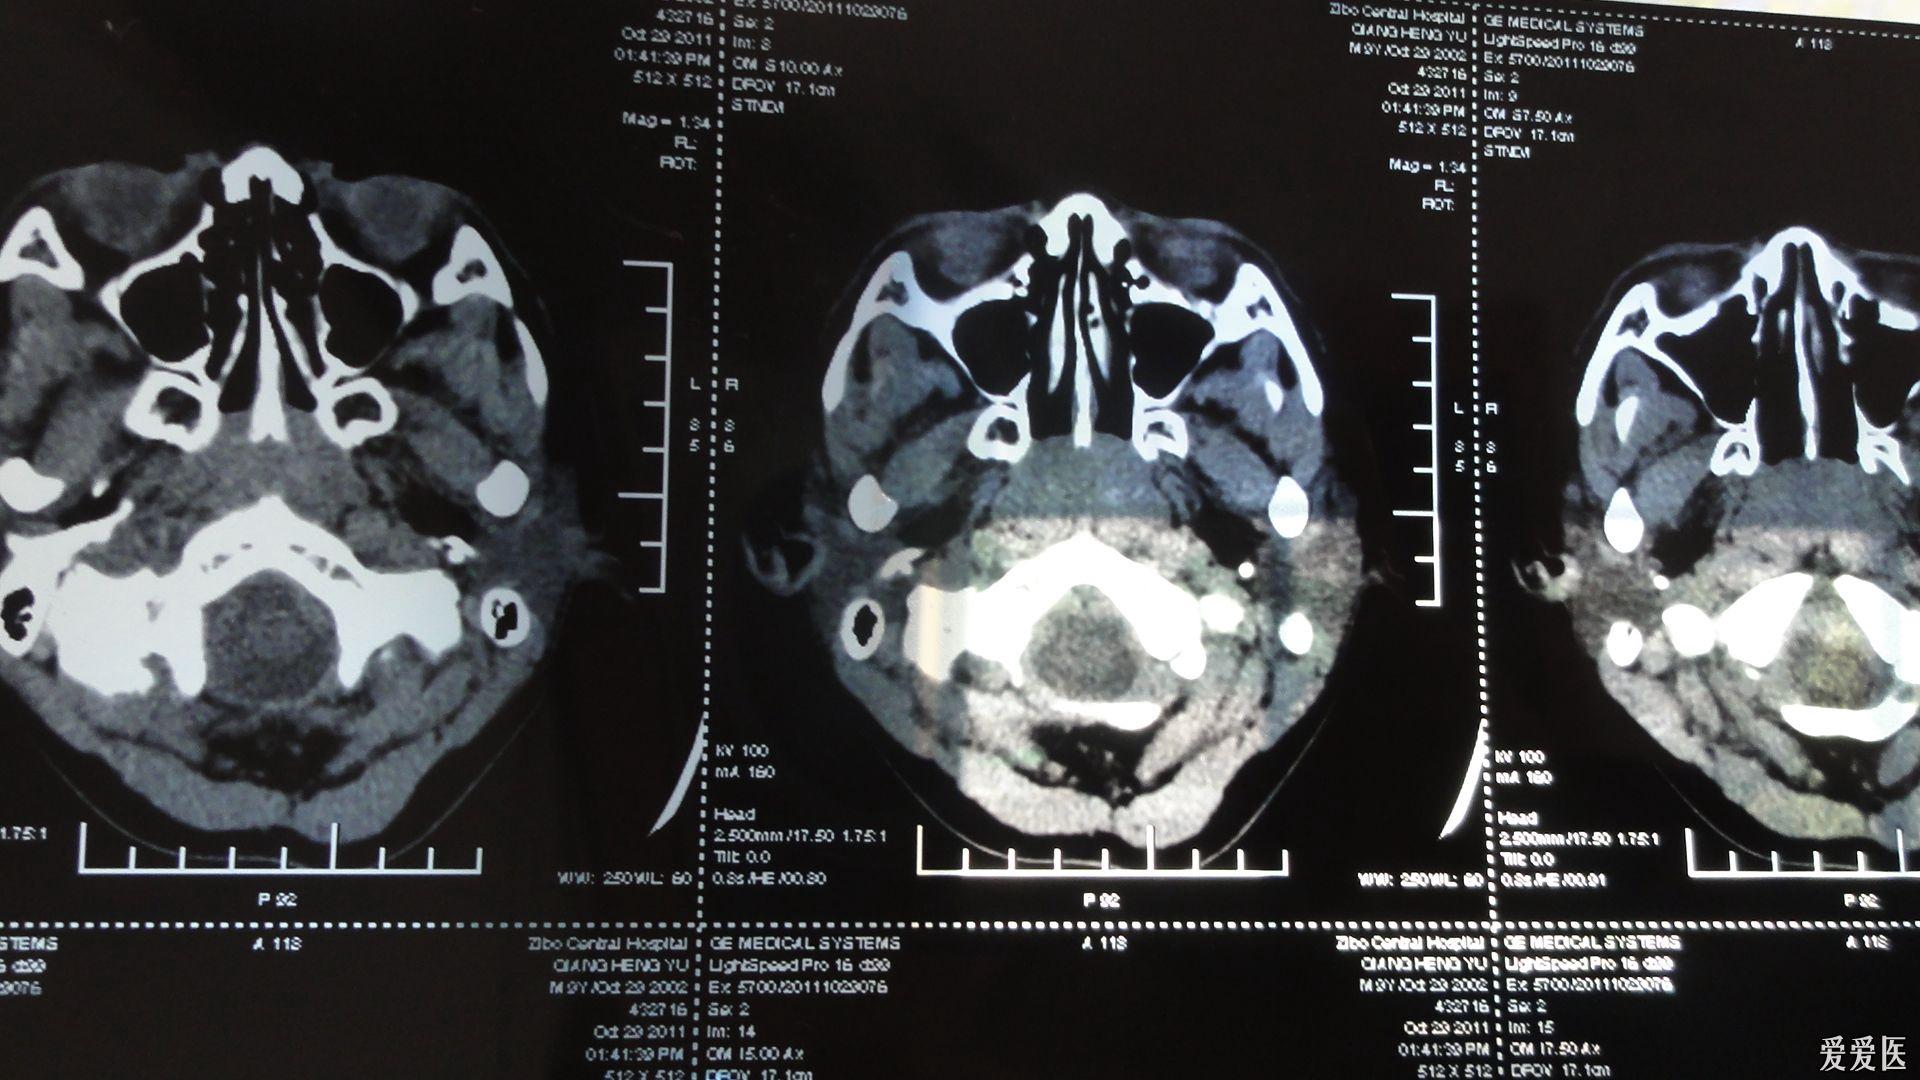

内科大夫求助增殖体肥大